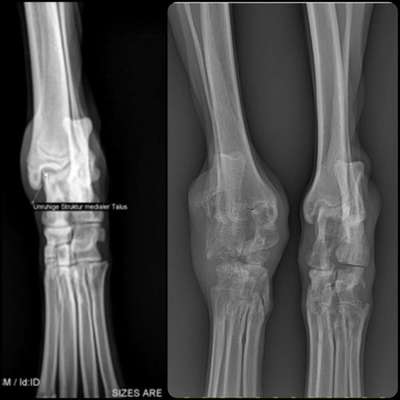

Hallo zusammen 🙋🏼‍♀️ Das ist Happy, 10 Jahre alt und mein Sorgenkind! Wie in der Überschrift schon steht, würde ich mich gerne einmal mit euch über dieses Thema austauschen. Vielleicht hat ja jemand auch diese Diagnose bekommen und kann oder möchte mir berichten! Durch eine unentdeckte und dadurch auch unbehandelte Leishmaniose bekam Happy die erosive Polyarthrtis. Das die Leishmaniose die Knochen derart angreift war mir nicht bewusst und somit ein riesen Schock für mich. Zur Zeit ist Happy in medizinischer Behandlung und bekommt Allopurinol (Gichtmittel) und purinarmes Futter! In regelmäßigen Abständen werden Ihre Blutwerte, Urin und natürlich die Hinterläufe kontrolliert. Zu den Bildern: Röntgenbild --> links ein gesundes Bein und rechts die beiden Hinterläufe von Happy Bilder mit Tape --> die Fehlstellung ihrer Hinterläufe vor ein paar Monaten, vom Physio getapt Orthese --> vor etwas mehr als einem Jahr haben wir eine Orthese anfertigen lassen, mittlerweile nicht mehr tragbar, weil das Gelenk dicker geworden ist